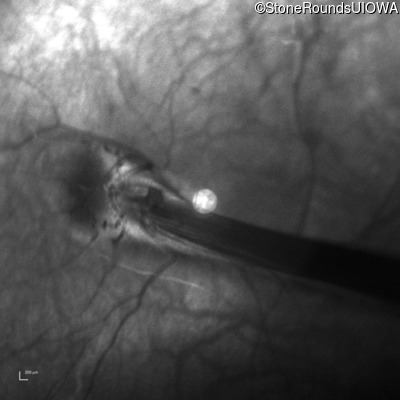

Infrared Fundus Photograph - Right - 20/125

Exemplar